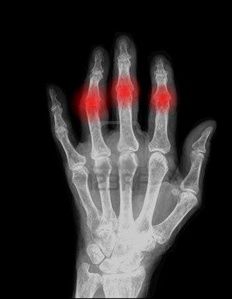

자가면역질환으로 알려져 있는 류마티스 관절염은 남성보다는 여성에게서 많이 발병하는 질환이다. 아직까지 원인이 불분명한 질환으로 류마티스 관절염이 발병할 경우 관절을 둘러싸고 있는 활막조직에 만성적으로 염증이 생기게 되며 연골과 뼈가 심하게 파괴되어 결국에는 관절의 기능이 떨어지고 변형이 찾아오게 된다.

류마티스 관절염이 발병할 경우 통증이 나타나는 관절이 빨갛게 부어 오르며 통증 부위를 눌러보게 될 경우 통증이 느껴지며 증상이 심한 경우에는 눌러보지 않더라도 통증이 느껴지고 관절을 움직이는 것도 힘들어진다.

증상이 심각해 질수록 활막 주위의 연골과 인대 등이 점차 파괴되어 관절이 제 역할을 못하게 되며 관절의 변형과 불구가 찾아오며 이렇게 관절 염증이 심한 사람들은 쉽게 피로감을 느끼며 심리적으로 불안감과 우울감을 느낄 수도 있다.